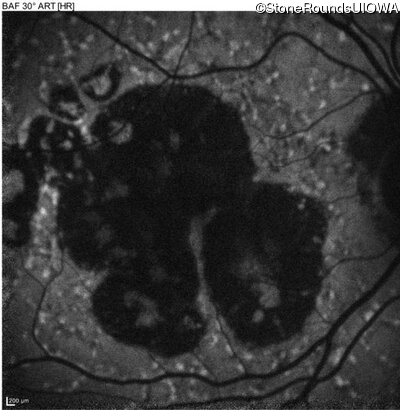

AR Stargardt Disease (IIA)

Age at visit: 59 years

This 59 year old man has noticed some blank spots near the center of his vision over the last 2 years.

AR Stargardt Disease ABCA4 Leu2027Phe CTC>TTC IVS30+1321 A>G AR